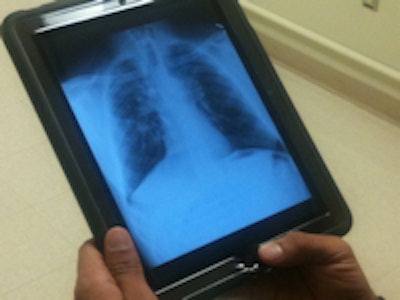

| Screening chest x-ray on iPad. Image courtesy of Frederick Weiss, MD. |